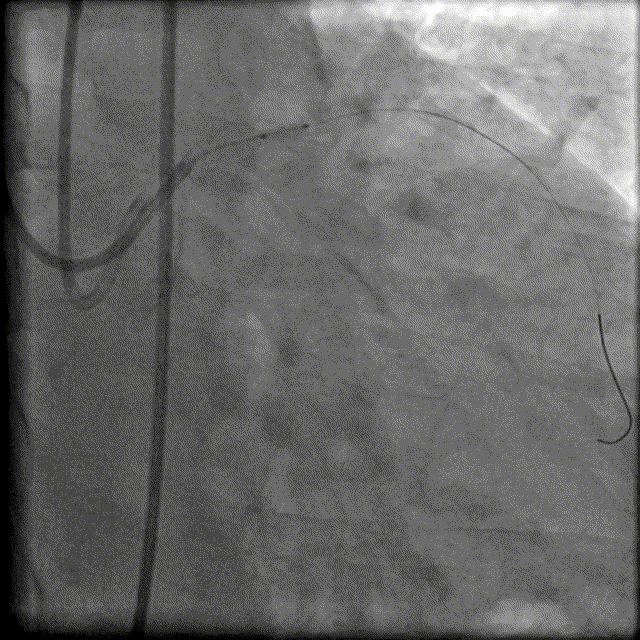

130cm Finecross微导管穿Runthrough 指引导丝到达RCA近端病变处,Fielder XTA、Pilot200指引导丝反复尝试无法通过RCA闭塞病变,随后尝试逆向侧枝开通RCA病变。

150cm Finecross微导管,Sion、Sion black指引导丝反复尝试无法通过LAD-RCA间隔支侧枝及心外膜侧枝血管有困难。

重复造影无造影剂渗漏。

换用较为粗大的心外膜侧。

换用Instantpass微导管(170cm)支撑下送Fielder XT-R导丝通过LAD-RCA心外膜侧枝逆向通过RCA闭塞病变,推送微导管后交换Gaia Third导丝,RCA正向送Telescope™导引延长导管进行主动迎接Gaia Third导丝。

建立轨道后,交换为Runthrough 导丝后,行IVUS检查证实导丝位于血管真腔。